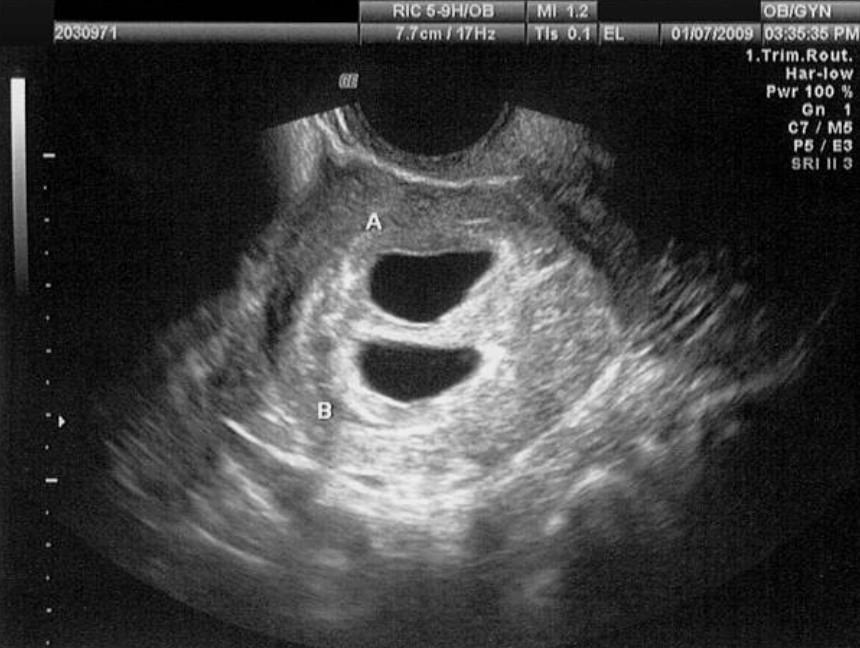

쌍둥이 임신은 크게 일란성(identical)과 이란성(fraternal) 쌍둥이로 나뉩니다. 일란성쌍둥이는 하나의 수정란이 분리되어 발생하며, 유전적으로 동일합니다. 태반과 태낭(임신 시 수정란을 둘러싸고 있는 조직)의 공유 여부에 따라 다양한 종류가 있으며, 일부는 태반이나 양막을 공유하여 특별한 관리가 필요합니다. 반면, 이란성쌍둥이는 두 개의 다른 난자가 각각 다른 정자와 수정되어 발생하며, 유전적으로 일반 형제자매와 같은 수준으로 유사합니다. 각각 독립된 태반과 태낭을 가집니다. 삼태아 이상의 다태아 임신에서는 위의 두 가지 유형이 혼합되어 나타날 수도 있습니다.

Screenshot 2025-04-12 at 23.01.39.png 다태아 임신은 일반 임신보다 여러 합병증 발생 위험이 높습니다. © Getty Images

다태아 임신의 위험 요소를 먼저 알아보자면, 다태아 임신은 일반 임신보다 여러 합병증 발생 위험이 높습니다. 임신성 고혈압과 전자간증은 다태아 임신에서 2-3배 더 흔히 발생합니다. 임신성 당뇨 또한 다태아 임신 시 위험이 증가합니다. 두 명 이상의 태아에게 철분 공급이 필요하므로 빈혈 위험이 높아집니다. 또한, 자궁경부무력증은 자궁에 가해지는 추가적인 압력으로 인해 조산 위험을 증가시킵니다. 또한 자궁이 더 크게 확장되어 분만 후 출혈 위험이 증가하는 경향이 있습니다.